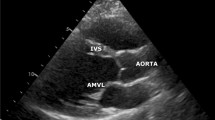

The conal malseptation, as a principal anomaly for TOF, has been extensively studied by morphological studies on postmortem specimens1,2,3,4,5,6. However, the objective quantification assessment of the conal malseptation by cardiac imaging modalities is still underutilized. There is one publication in the late 80 s using 2D echocardiography that studied the aortic root displacement to the right (dextroposition) in TOF patients and they measured the values of the aortic valve rotation angles in the normal population compared with TOF patients. The aortic root rotation angle was 23.4 ± 8.3° in normal subjects, while in TOF patients have higher clockwise rotation angles; 59.2 ± 10.7°2. The RVOT underdevelopment was not assessed or quantified in this study.

Our data is also in agreement with the 2D echocardiography study performed on 22 TOF patients, which demonstrated a clockwise rotation with a rightward displacement of the aortic root due to the lack of conal rotation2. However, no assessment of RVOT development was performed in this study which could be explained by the limited acoustic window of echocardiographic examination.